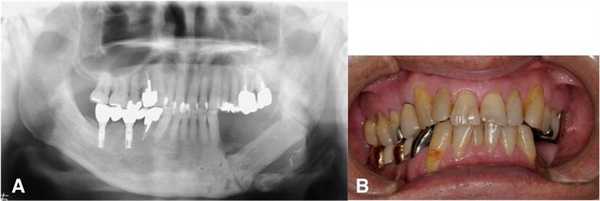

На ортопантомограмме контурировалась слабо демаркационная зона деструкции костной ткани в области имплантатов на месте 35 и 36 зубов, при этом поражение достигало нижнего края челюсти, что в результате спровоцировало возникновение патологического перелома. Вокруг имплантатов с правой стороны челюсти никаких патологических поражений отмечено не было (фото 2). С помощью КТ-сканирования удалось подтвердить деструкцию нижней челюсти слева и наличие линии перелома через всю толщу костной ткани (фото 3).

Фото 2. Ортопантомограмма пациента до лечения.

Фото 3. КТ-изображения нижней челюсти с левой стороны: а) аксиальный срез в области левого первого моляра; b) корональный срез в области левого первого моляра.